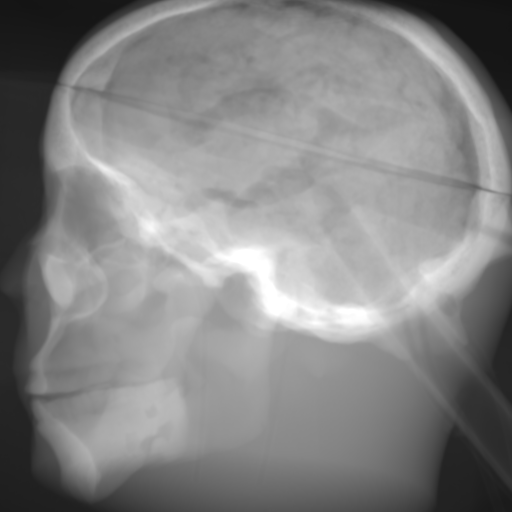

(a) Input: MR proj.

Refer to caption

(b) Output: U-net p-loss.

(c) Output: ResNet p-loss.

(d) Output: CRN p-loss.

(e) Reference: X-ray proj.

Figure 2: Results of the projection synthesis. Top row: Results generated with the perceptual-loss function. Bottom row: Results generated with the 1subscript1\ell_{1}-loss function.

The quantitative and qualitative results of the proposed experiments are presented in Table I and Figure 2. By examining these it can be observed that the differences in the calculated MSE of all network architectures and incorporated loss functions are only small. The best results in terms of pixel-wise deviation could be achieved with the ResNet architecture combined with the 1subscript1\ell_{1}-loss function. This network achieves a deviation from the reference of only 0.058, i.e., 2.4 percent. Also the results of the U-net and CRN networks are still good with deviations of 2.6 and 2.9 percent. Similarly small variation can be observed in the structured similarity measure. The ResNet and CRN exhibit approximately equal quality with SSIM measures of 0.938 and 0.920 for the 1subscript1\ell_{1}-loss and 0.924 and 0.931 for the perceptual-loss, respectively. The results generated with the U-net are slightly worse. The highest peak signal-to-noise ratio is achieved by the ResNet (1subscript1\ell_{1}-loss), followed by the U-net (1subscript1\ell_{1}-loss) and CRN (p-loss). It is noteworthy that the ResNet and U-net both achieve the highest results in all error metrics using the 1subscript1\ell_{1}-loss while the opposite is the case for the CRN which works best with the perceptual-loss function.

Overall, the perceptual-loss achieves competitive and in some cases even better results than the 1subscript1\ell_{1}-loss when comparing the pixel-wise error metrics. For example, the cascaded refinement network’s MSE is 0.013 smaller for the perceptual- than for the 1subscript1\ell_{1}-loss. This might be suspicious at first sight, considering that the 1subscript1\ell_{1}-loss purely optimizes for this pixel-wise error in the training process while the perceptual-loss compares the raw feature activations of the evaluation network. Contrarily, this behavior cannot be observed for the U-net and ResNet. The results produced with the 1subscript1\ell_{1}-loss achieve higher values for all error measures for these networks. An explanation for this obervation is that the intensity values of the input image still cause an impact on the respective layers output in the evaluation network when computing the perceptual-loss. Consequently, these differences also transition to the computed loss value for all feature layers. Even though the perceptual-loss incorporates the raw intensity values, it is not guaranteed that the scaling of these is conserved in this process. By this, the relative changes can be similar, whereas the absolute range of values changes and, correspondingly, also the pixel-wise error metrics.

Another observation is that the perceptual-loss is able to conserve high-frequency details in the image. The fine line in the projection images that forms a circle around the cranium is visible in the input (Figures 2a & 2f), as well as in the label images (Figures 2e & 2j), and also in the images generated with the perceptual-loss function (Figures 2b2c, and 2d). In contrast, all generators ”loose” this line when the 11\ell 1-loss is applied (Figures 2g2h, and 2i). This effect is also qualitatively observable in other parts of the images. Despite achieving equal or better results regarding the error metrics, the generally less sharp look of the results generated with the 11\ell 1-loss function is apparent. This behavior is in accordance with previous observations that concluded that an perceptual-loss leads to sharper images than a comparable 11\ell 1-loss [19]. Considering the common applications of X-ray Fluoroscopy, e.g., interventional guidance for stents and similar devices, high spatial resolution is a key requirement. Utilizing a loss function that is able to preserve high-frequency details in the images is desirable to this end. The perceptual-loss appears to be suited for this task as presented in our evaluation.